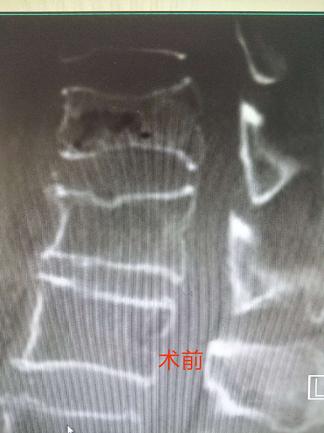

患者为一84岁男性,曾上朝鲜战场抗美援朝。就医前两周因坐车颠簸而致腰部疼痛,不能下地行走,自行卧床休息后疼痛无明显缓解,影响饮食和睡眠,至本院门诊就诊,查DR和CT确诊为腰1椎体压缩性骨折,收住院治疗。副院长、骨科主任医师朱兴元诊疗小组接收患者后,组织全科讨论,为患者制定了详细的手术计划。7月16日,在麻醉科监护下手术团队为患者施行了经皮单侧椎弓根穿刺全椎体成形术。手术仅耗时不到一小时便取得圆满成功,术后两小时患者即可下地自主行走,术前疼痛症状完全消除,两日后康复出院。